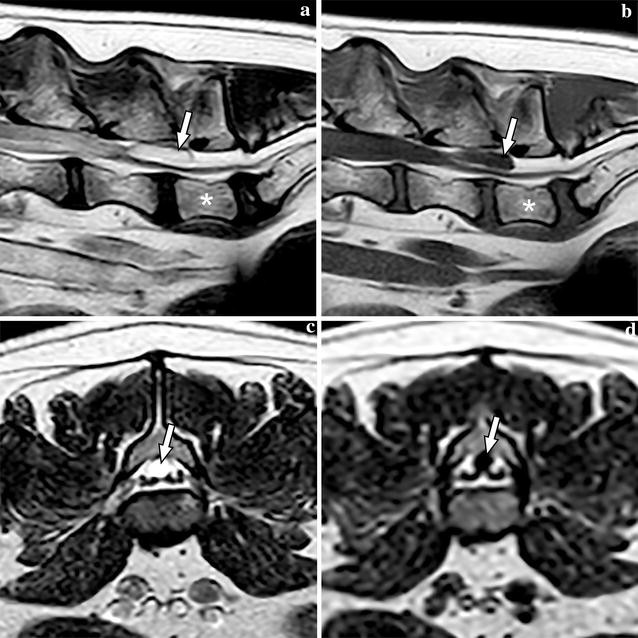

An 8-year-old female French Bulldog weighing 12.4 kg was referred to the Department of Clinical Sciences of Companion Animals at Utrecht University with a history of intermittent faecal incontinence and progressive abnormal gait in the hind limbs since 3 months. Conservative treatment with corticosteroids initially showed improvement but after tapering the dosage, clinical signs recurred. The owners felt that the dog was in pain because they found the dog progressively more depressed/lethargic. On general examination, the dog showed signs related to brachycephalic obstructive airway syndrome. Orthopaedic examination elicited pain on palpation and extension of the L6 to S3 region. Neurological examination identified hind limb ataxia and ambulatory paraparesis and postural deficits in the hind limbs, more severe on the left side. Spinal reflexes were normal in all limbs. The neuroanatomic localization based on the neurological deficits included T3–L3 and based on the lumbosacral pain on palpation and faecal incontinence it was extended until S3. Magnetic resonance imaging (MRI, type Ingenia 1.5T, Philips, Eindhoven, The Netherlands) was performed under general anaesthesia of the thoracolumbar, lumbar and lumbosacral spine extending from T6 to Cd3 with sagittal and/or transverse T1-weigted, T2-weighted, T2*-weighted, fluid attenuation inversion recovery (FLAIR) and short tau inversion recovery (STIR) sequences (Fig. 1). At the level of L6–L7 an oval cyst-like structure was seen with dorsal compression of the cauda equina. The content of this structure was isointense with CSF. An ill-defined T2W hyperintensity was present within the spinal cord at the level of T12, most likely consistent with oedema and less likely fibrocartilaginous embolism due to the insidious onset and progressive ataxia. Kyphosis and multiple thoracic hemivertebrae were noted, consistent with breed related vertebral column deformities, without evidence of spinal cord compression. The radiological diagnosis was a cyst-like structure with dorsal compression of the cauda equina. In addition, all visible intervertebral discs showed decreased hypointense signal compatible with intervertebral disc degeneration. Mild disc protrusion was found at multiple levels, but there was no disc-associated compression of the spinal cord or cauda equina.

Magnetic resonance images of the caudal lumbar vertebral column of Case 1, including T2-weighted sagittal (a), T1-weighted sagittal (b), T2-weighted transverse (c), and FLAIR transverse (d) images. The meningeal cyst is marked with an arrow on all images and L7 is labelled with an asterisk on images (a) and (b)